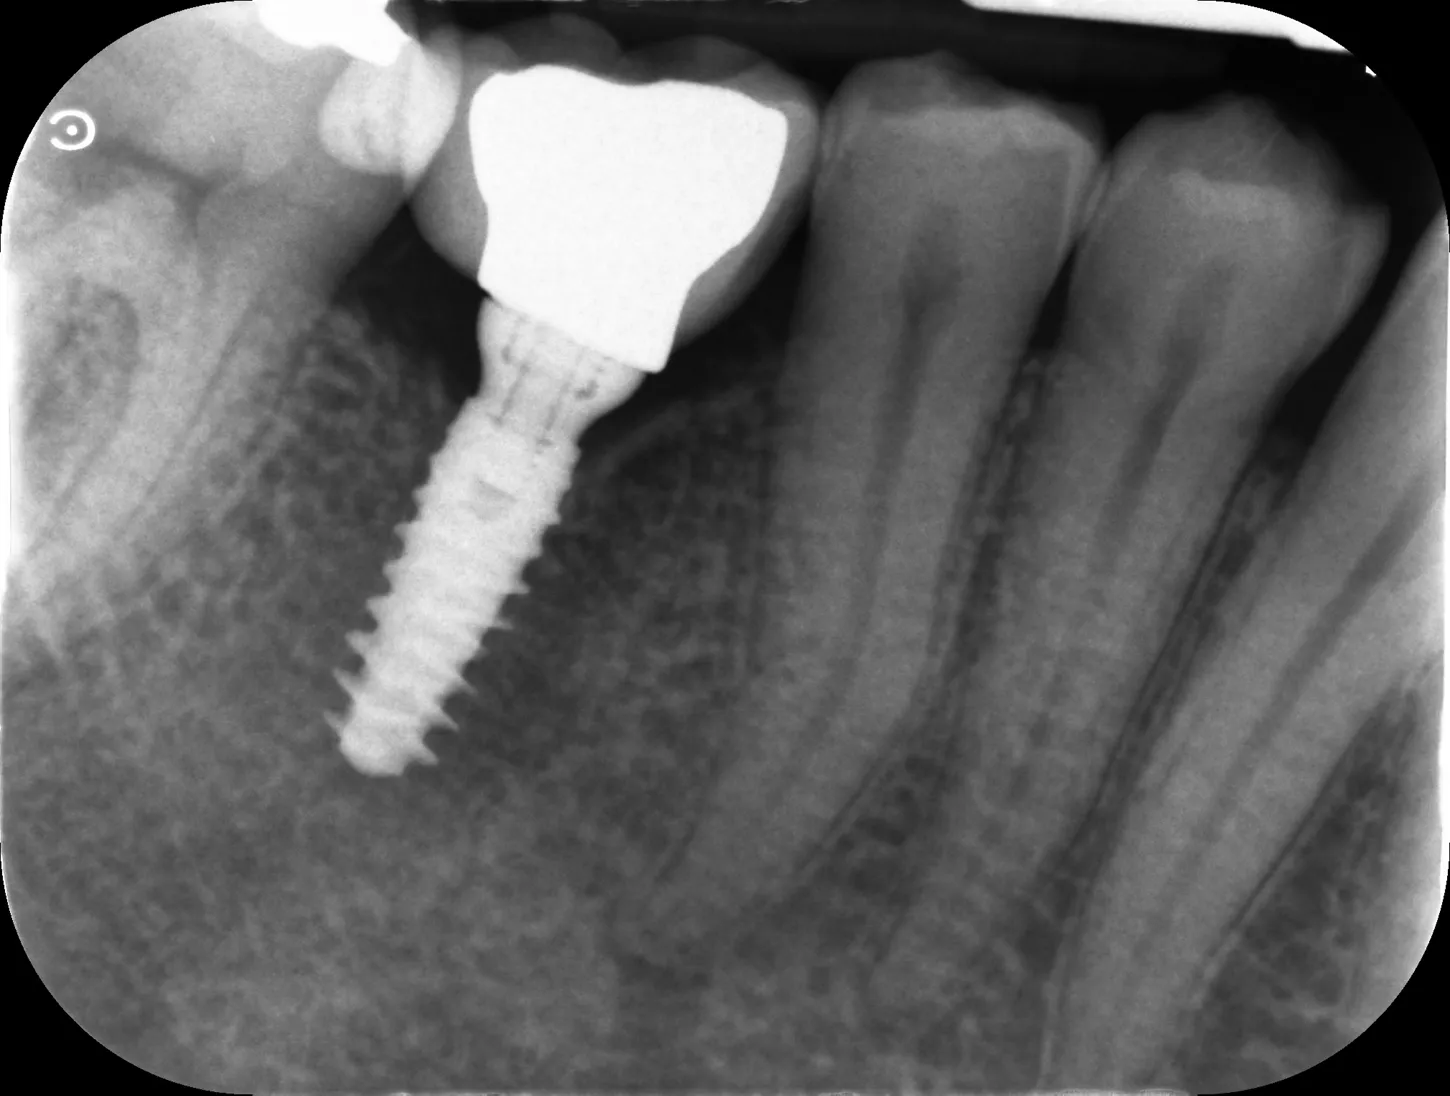

16. Radiographie de contrôle de la restauration finale.